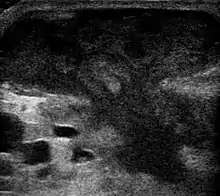

An abscess is a localized collection of pus (purulent inflammatory tissue) caused by suppuration buried in a tissue, an organ, or a confined space, lined by the pyogenic membrane.[22] Ultrasound imaging in the emergency department can help in a diagnosis.[23] It is; however, more useful to rule out than rule in an abscess.[24]